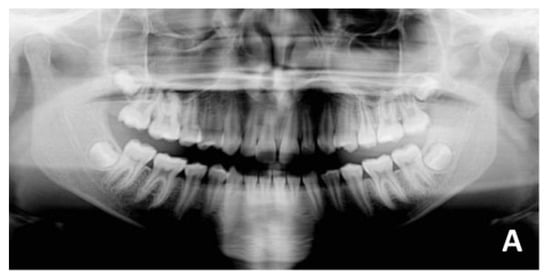

3. Case Report Number 1

The first case reported was an adult male patient who had already undergone orthodontic treatment in the past with the extraction of the four first premolars. The orthodontic situation (Figure 9, Figure 10 and Figure 11 and Table 1) showed a dentoskeletal class II malocclusion, upper and lower crowding, severe deep bite with impingement of the lower incisors on the palate, retroclination of the upper and lower incisors, and convex and biretruded profile. The patient was strongly brachyfacial, and therefore, a deep bite was not only dental but also skeletal. The patient showed good exposure of the upper incisors; therefore, in the resolution of the deep bite, it was preferable not to intrude upper incisors in order not to worsen the patient’s aesthetics.

The treatment was conducted exclusively with clear aligners and followed the protocol for the resolution of the deep bite that was described above. It lasted approximately 18 months, with only one little refinement. At the end of the treatment, the resolution of the deep bite and an important leveling of the patient’s curve of Spee was clearly evident, as can be seen in the comparison between the initial and final orthopantomography.

Figure 10. Pre-treatment radiographic of case number 1: (A) orthopantomography; (B) lateral cephalogram.